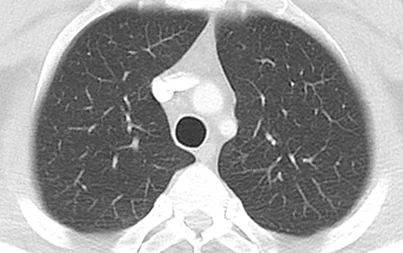

左が正常の胸部CT写真,右が過敏性肺臓炎のCT写真です。粉雪のような淡い白い影が肺全体に広がっていることがわかります。淡い影のため,レントゲンではあたかも正常のように見えてしまうこともありますが,胸部CTでは見逃すことは

(Case courtesy of Bruno Di Muzio, Radiopaedia.org, rID: 41162)

ありません。この画像を見た場合には,クリニックではできない検査をうけてもらうために総合病院に紹介となります。